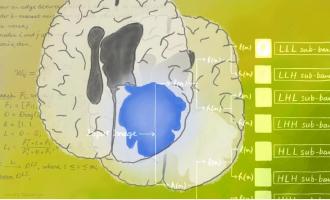

Actualité publiée le 24/06/2020TUMEUR CÉRÉBRALE : La radiomique au service du diagnostic

Actualité publiée le 11/06/2020